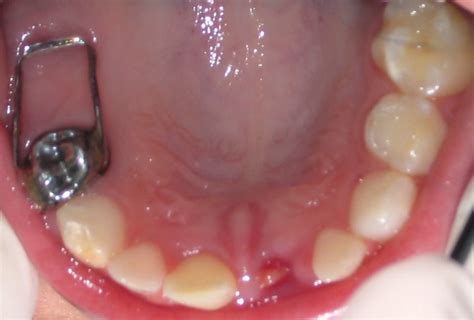

Es un aparato fijo utilizado para mantener el espacio creado por la pérdida prematura, por ejemplo, de una Segunda Molar Temporal.

La zapatilla distal actúa como un mantenedor de espacio, previniendo que los dientes adyacentes se desplacen hacia el espacio vacío. Al hacer esto, se asegura de que haya suficiente espacio para que el diente permanente erupcione correctamente.

La zapatilla distal puede usarse para vestibularizar piezas inferiores y como opción para la expansión.